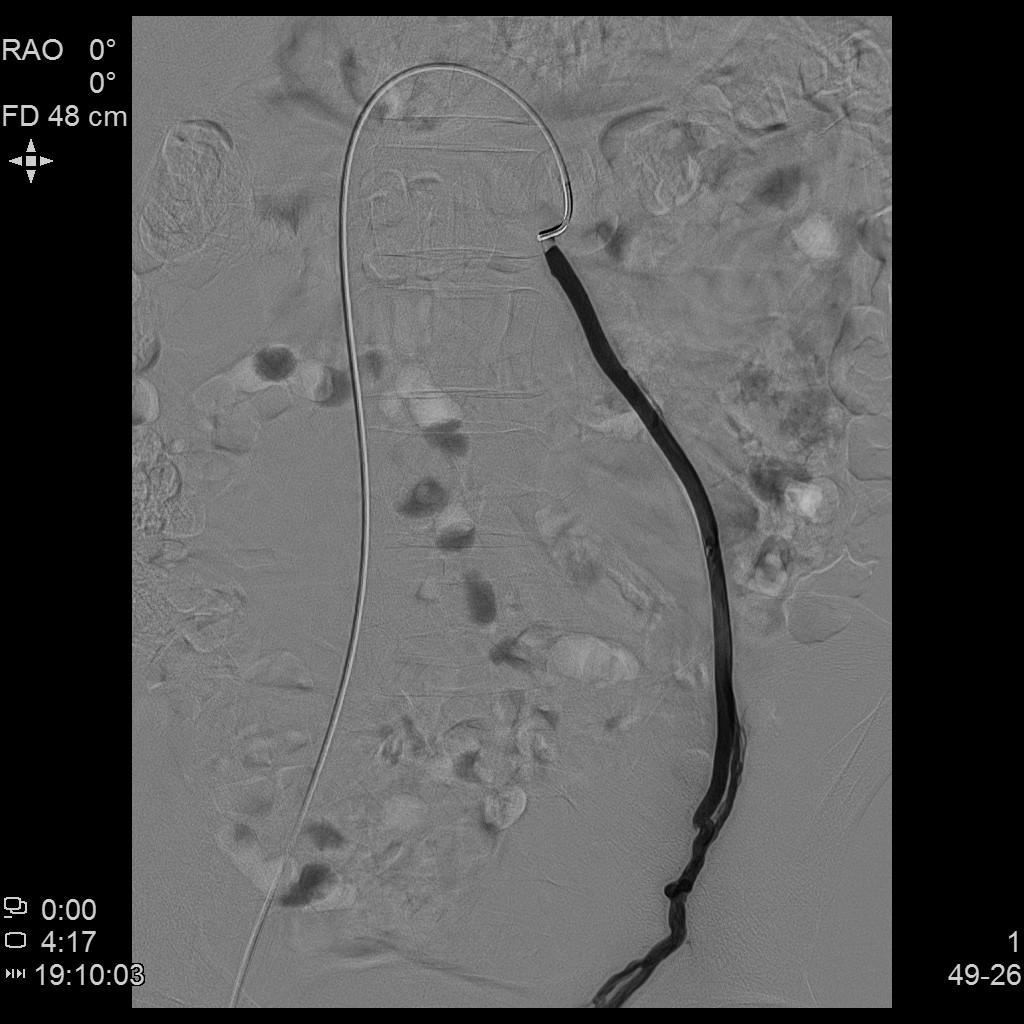

- 行左侧精索静脉造影显示左侧精索静脉明显扩张、迂曲,血流逆流。予以超选插管至左侧精索静脉中下段行弹簧圈栓塞+泡沫硬化栓塞治疗。复查造影显示左侧精索静脉主干闭塞。

左侧精索静脉造影1